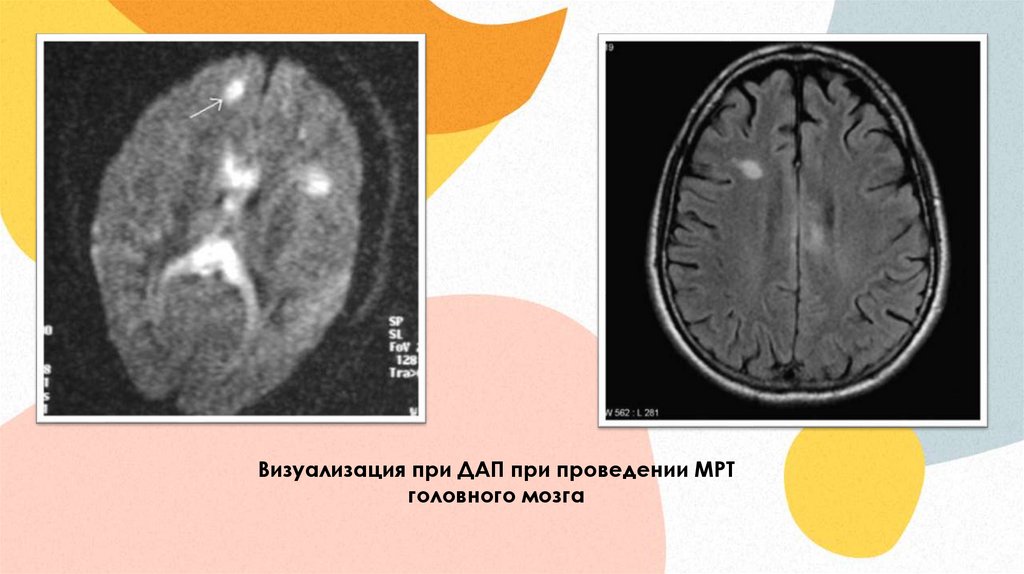

Визуализация при ДАП при проведении МРТ

головного мозга